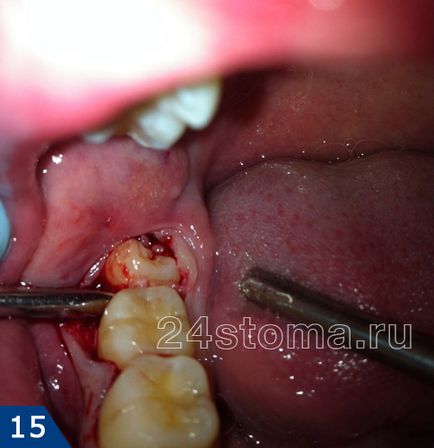

В чому полягає складність складного видалення

Як правило, в цих випадках доктору доводиться робити розріз ясен, щоб відшарувати її від кістки. Відразу після цього за допомогою бормашини висвердлюється певний обсяг кісткової тканини навколо кореня зуба. Останнє дозволяє створити доступ до обламаної верхівці кореня або прибрати нависає над викривленою частиною кореня ділянку кісткової тканини. Іноді буває необхідно розпиляти межкорневой перегородку, щоб провести видалення коренів зуба поодинці.

на фотографіях показаний процес складного видалення ще непрорезавшійся зуба. Пояснення до кожної фотографії з'являються при натисканні на фото.